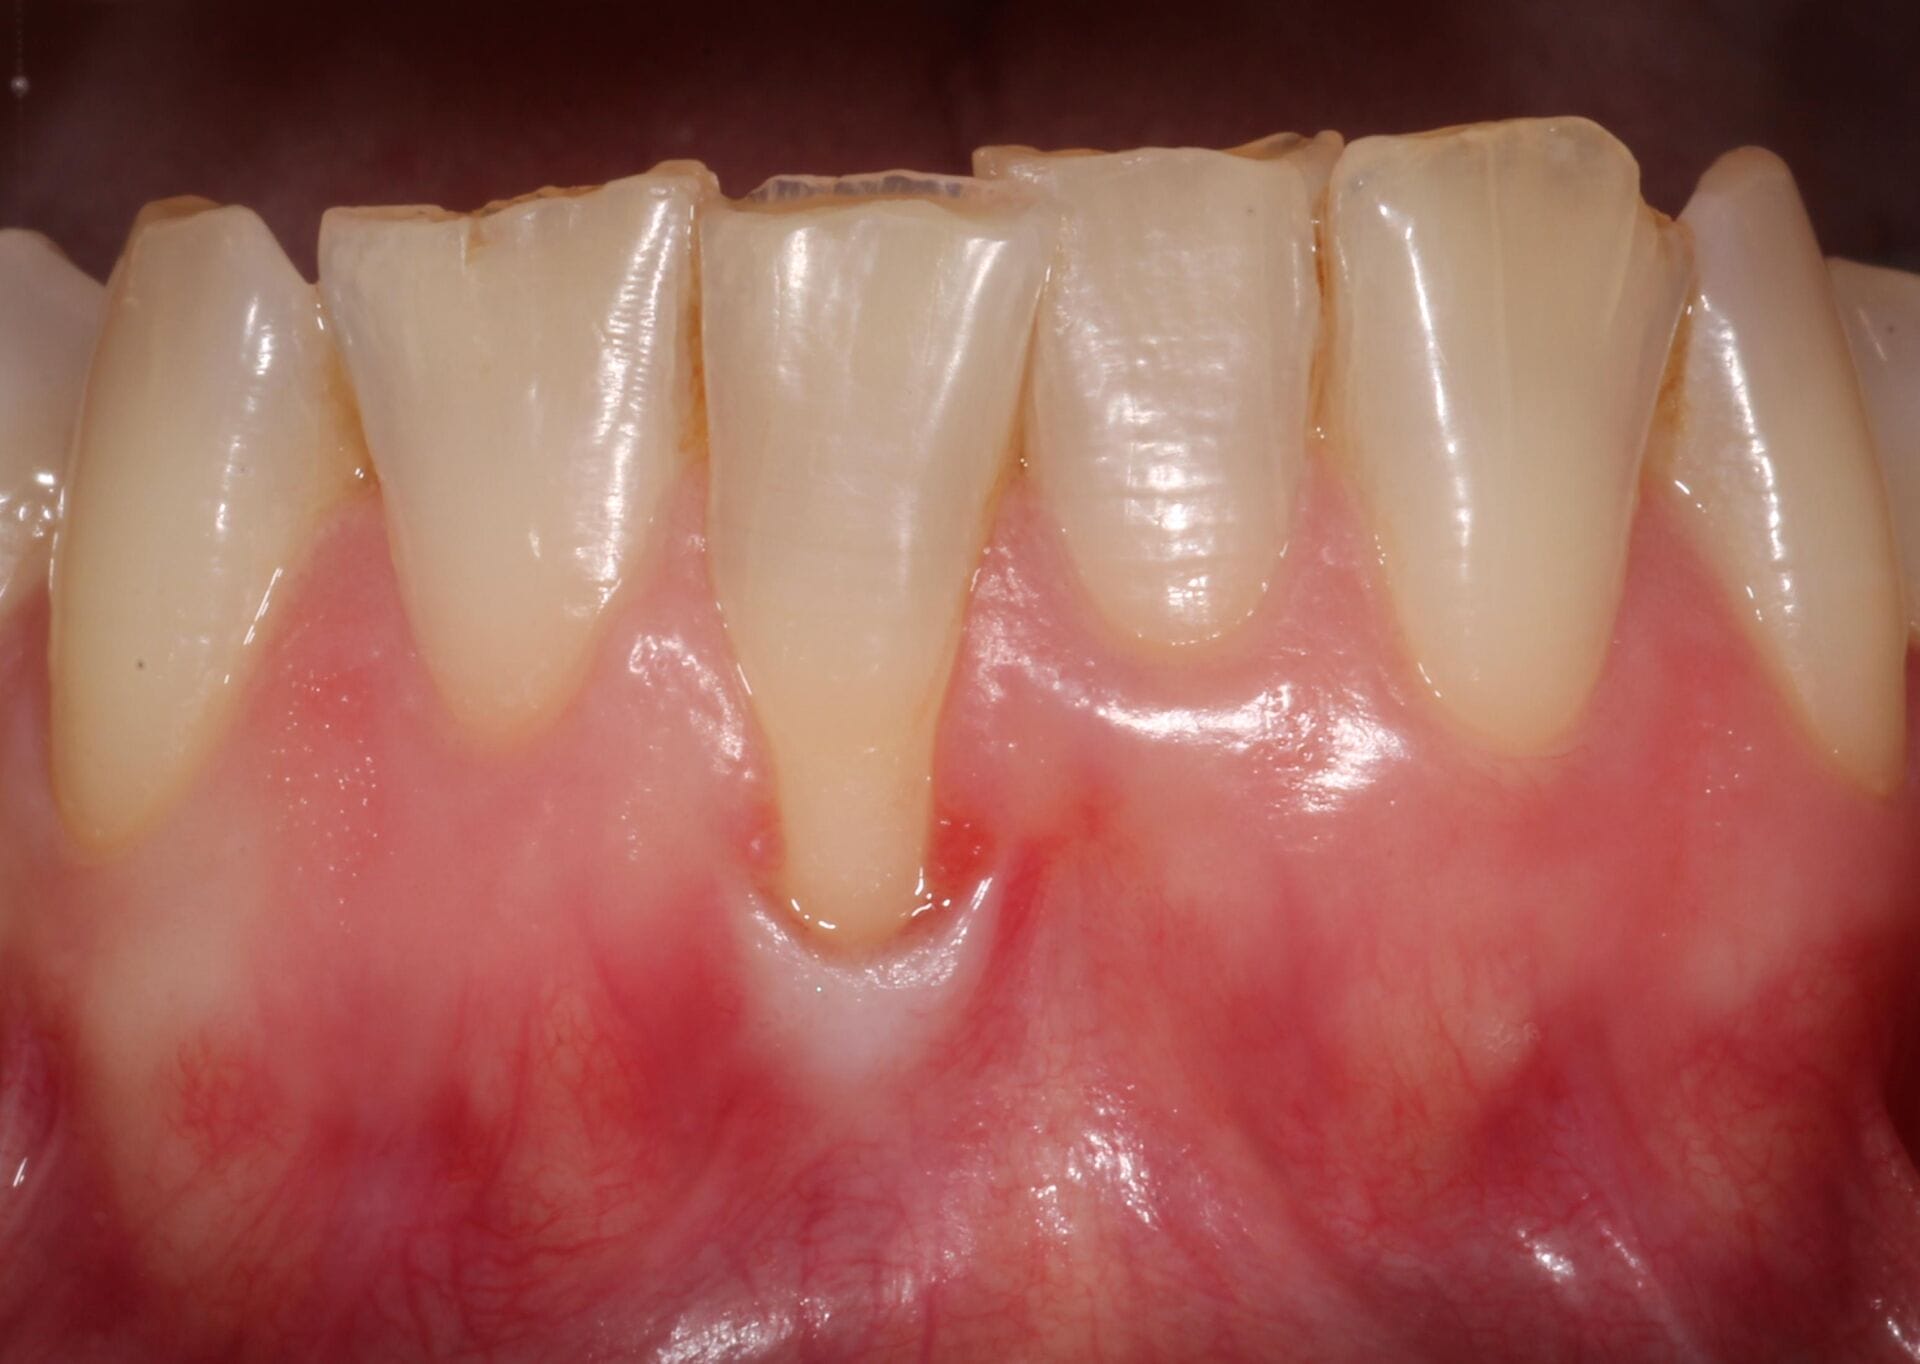

Periodontitis is the advanced form of gum disease. It develops when inflammation from untreated gingivitis spreads below the gumline, destroying the connective tissue and bone that anchor your teeth. Symptoms can include:

Gum recession

2.Gum Graft Surgery

In cases of gum recession, a gum graft can help restore protective tissue around the teeth. Tissue—often from the roof of your mouth—is grafted onto the affected areas, helping to reduce sensitivity, improve appearance, and prevent further recession.